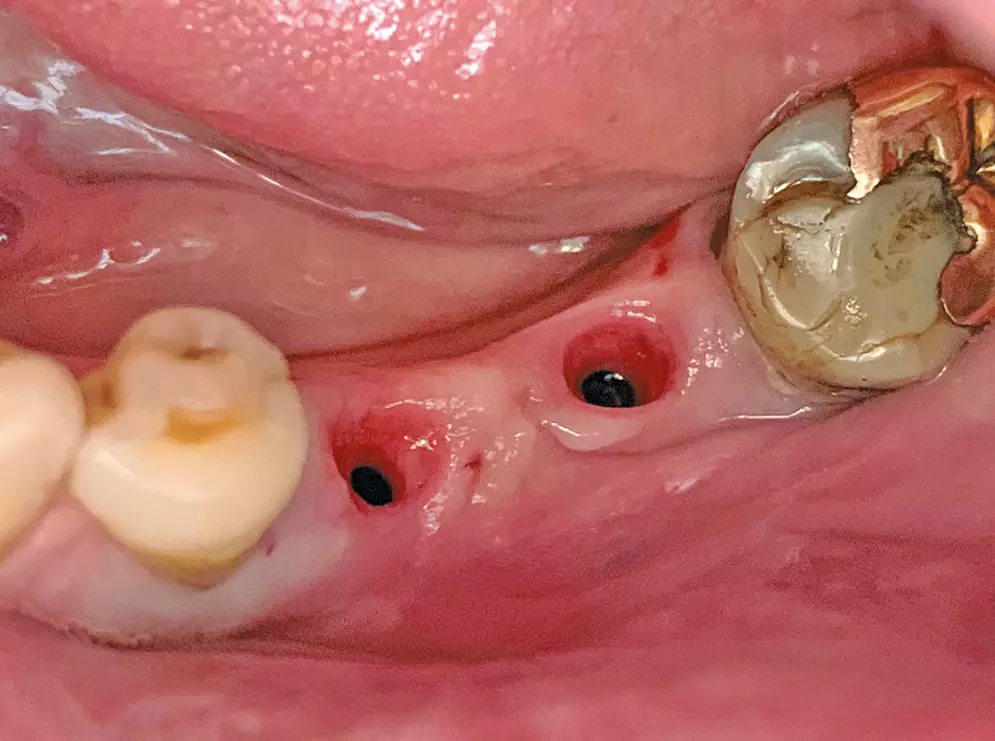

Verschraubung der mit dem Abutment verklebten Restauration direkt im Implantat

Ein weiterer Vorteil ist darin zu sehen, dass nur eine Verschraubungseinheit vorliegt, deren Schraubenkopf zudem tief an der Basis des Abutments angeordnet ist und einen relativ kleinen Durchmesser aufweist. Damit lässt sich der okklusale Zugang in gleicher Weise wie oben erwähnt verschließen und ein günstiger kosmetischer Effekt erzielen (Abb. 5a-d).